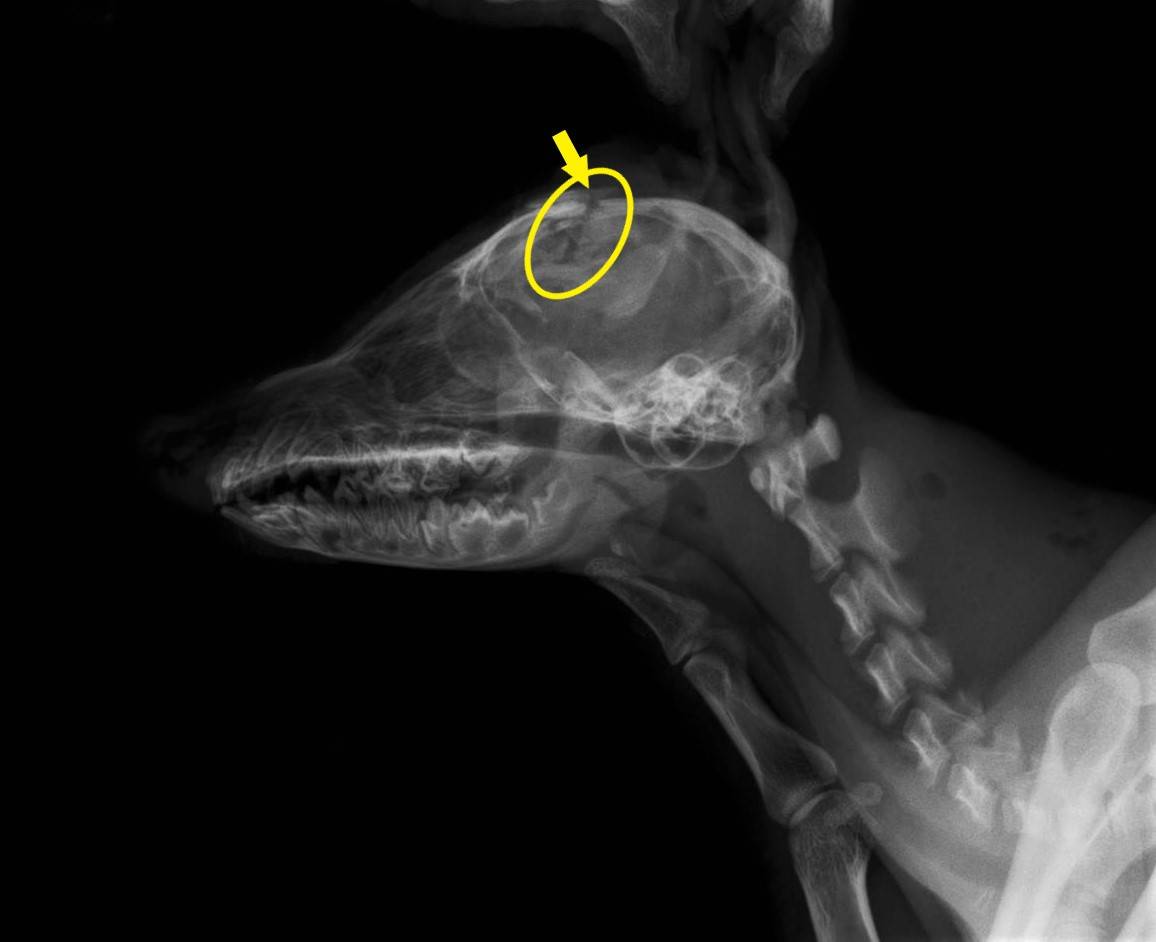

これは、今年の8月に保護された幼タヌキの頭部のX線写真です。

このタヌキは、鼻梁から前頭部にかけて深い咬傷を負い、その下の頭蓋骨が粉砕骨折していました(黄色矢印の色が黒く抜けた部分)、皮膚の裂開部からは、脳の一部が露出する大怪我でした。